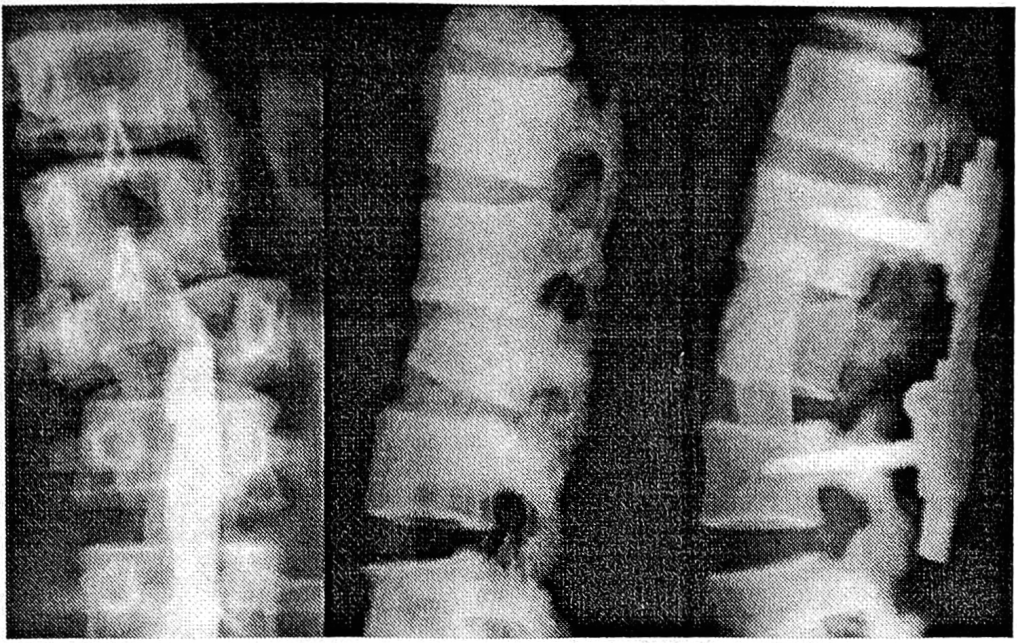

Принимая во внимание относительно небольшой диаметр корней дуг верхне- и среднегрудного отделов, мы отдавали предпочтение применению на этом уровне комбинированной конструкции, комплектуемой из нижних транспедикулярных винтов и верхних пароссальных педикулярных и ламинарных крюков. В грудопоясничном и поясничном отделах фиксацию, как правило, производили только «чисто» транспедикулярными имплантатами. Особенности многоплоскостной интраоперационной репозиции и коррекции с помощью металлоконструкции и этапность ее выполнения зависели от характера, вида повреждения и степени нарушения анатомических взаимоотношений в позвоночном сегменте. При оскольчатых переломах тел позвонков и передних переломовывихах производили интраоперационную гиперэкстензионную репозицию с последующей дозированной дистракцией под контролем ЭОП (рис. 3).

Рис. 3. Рентгенограммы позвоночника больного с передним переломовывихом L2—3 позвонков до операции, после операции и через 2 года после удаления фиксатора «Медбиотех».